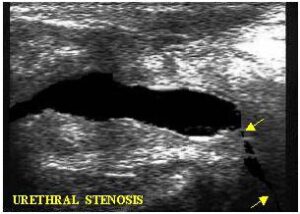

Uretra

Nel soggetto normale, all’imbutizzazione del collo fa seguito la morbida distensione dell’uretra prostatica. Nelle uretriti la distensione appare rigida e le pareti notevolmente iperriflettenti. Nel caso di restringimenti (stenosi) dell’uretra a valle, il sintomo indiretto apprezzabile è l’iperdilatazione nella sua porzione prostatica (foto 10).